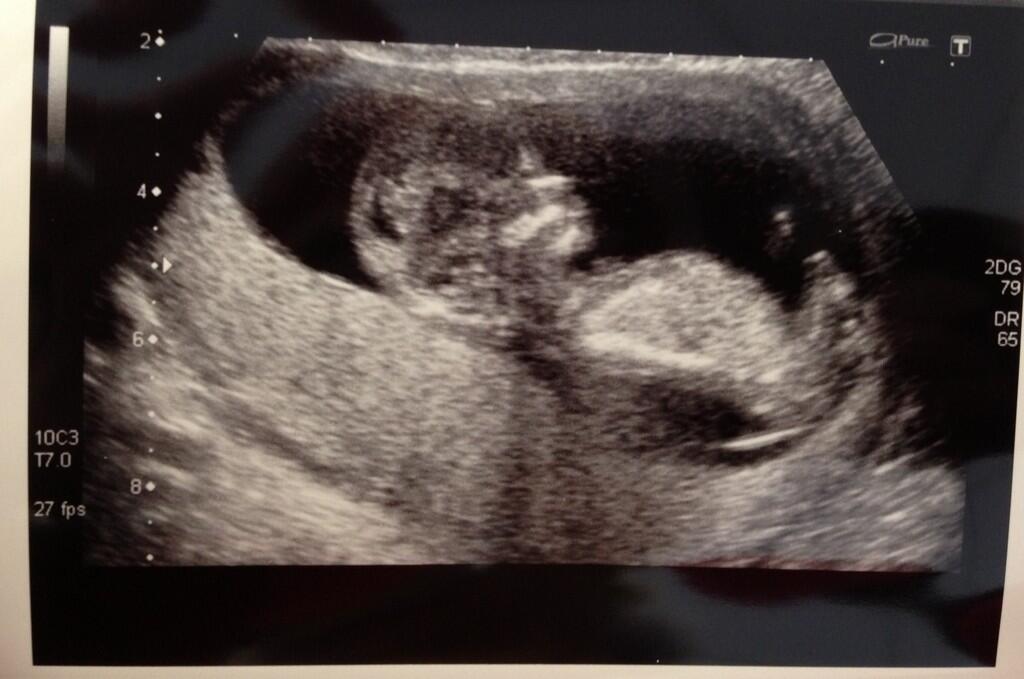

room and I made myself comfy on the table. The sonographer put the wand to my stomach and there on the

screen was baby bopping around.

Everything looked good and after a bit of wiggling on my

part, the sonographer managed to get an NT length of 1.6mm. She concluded that I was measuring not 12

weeks 4 days as per my normal cycle length, but 13 weeks 4 days! If I am honest

I think the reality is probably somewhere in the middle. I do not think it is possible for me to be a

whole week ahead as I am pretty sure I know when I ovulated, give or take a

couple of days. Of course it doesn’t

really matter. This baby will arrive

when he or she is ready. It just makes it more complicated when people ask how

far along you are. For the time being I

have decided to go somewhere in the middle and say I was 13 weeks exactly on scan

day. This would give me an estimated due

date of 27th/28th November.